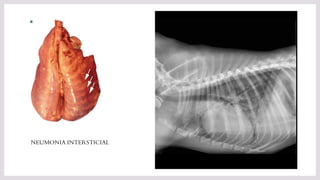

NEUMONIA INTERSTICIAL